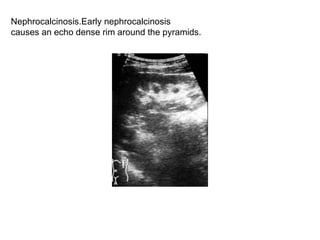

Nephrocalcinosis.Early nephrocalcinosis  causes an echo dense rim around the pyramids.